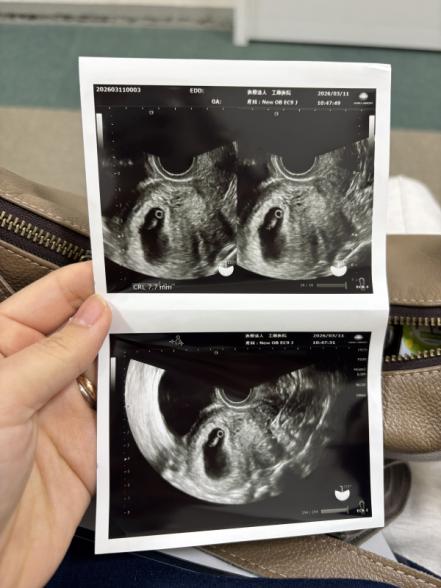

6週の時のエコーで胎芽と心拍確認できました。

このエコー写真は正常ですか?

卵黄嚢が見えていて、その近くに赤ちゃんの姿も確認できていましたね。

大きさも週数相当のものになるのではないかと思いました。

順調に経過されているように思いました。